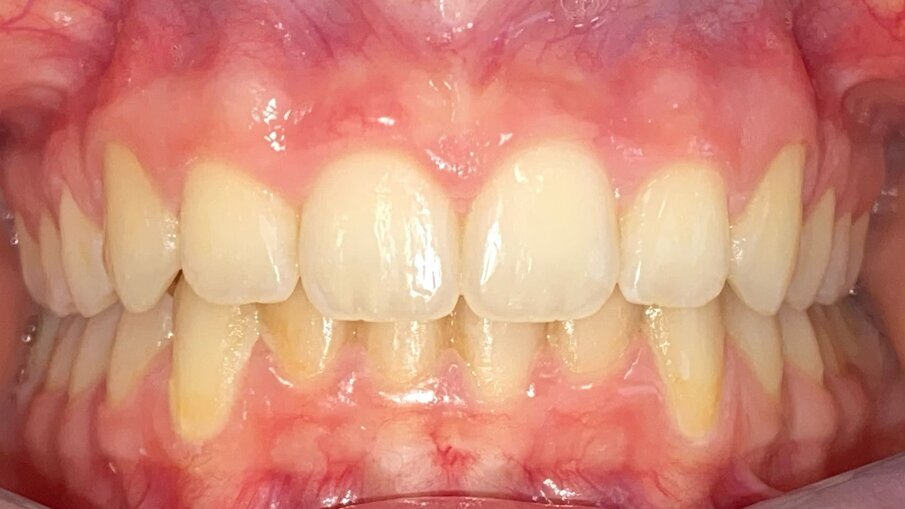

All’esame obiettivo intraorale si riscontra sul piano frontale un severo morso profondo con precontatto traumatico degli incisivi superiori contro la papilla retroincisiva e le rughe palatine anteriori durante la massima intercuspidazione, con overbite di 10 mm (Fig. 5). Dalle foto laterali si evidenzia una malocclusione di Classe II divisione 2 con scissor bite dell’elemento 1.5 (Figg. 6, 7), mentre dalle foto occlusali si rileva un grave affollamento con contrazione di entrambe le arcate maggiore nella zona premolare (Figg. 8, 9). L’analisi di Bolton mostra un eccesso superiore 3-3 di 2,34 mm (73,6%) e 6-6 di 2,76 mm (88,8%). L’analisi cefalometrica evidenzia una Classe II scheletrica, modello facciale normodivergente, angolo interincisale aumentato, incisivi superiori e inferiori retroinclinati (Fig. 10). La radiografia panoramica mostra la presenza dei germi dei terzi molari, assenza di parallelismo tra le radici dei premolari inferiori (Fig. 11) e una sovraeruzione degli incisivi inferiori che crea un doppio piano tra gli incisivi e i molari, segno di una curva di Spee molto profonda.

Fig. 5_Frontale pre-trattamento.

La durata totale del trattamento è stata di 12 mesi, il risultato è stato ottenuto grazie a una pianificazione computerizzata dettagliata e a scelte terapeutiche accurate, unite a una biomeccanica appropriata per la malocclusione nei tre piani dello spazio. Il sorriso della paziente ha ottenuto un miglioramento estetico evidente, con il riempimento dei corridoi buccali, una corretta esposizione degli incisivi e un miglioramento del profilo grazie alla proiezione del pogonion cutaneo e alla coincidenza delle linee mediane (Figg. 14-17). I dati clinici finali evidenziano un rapporto bilaterale di Classe I ottenuto grazie al preciso timing di inizio della terapia. Sono stati normalizzati gli eccessi di overjet (2,5 mm) e overbite (2,5 mm), risolvendo così il severo morso profondo (10 mm) e correggendo la curva di Spee. In entrambe le arcate è stato ottenuto un buon allineamento dentale, il ripristino della forma dell’arcata e la correzione dello scissor bite (Figg. 18-23). Le relazioni scheletriche sagittali sono migliorate con una normalizzazione del rapporto sagittale mandibolare A-N-B a 4° e un indice di Wits di 2 mm. Da un punto di vista delle relazioni verticali, l’inclinazione mascellare è rimasta pressoché invariata, così come l’inclinazione mandibolare. Per quanto riguarda i rapporti dento-basali, l’inclinazione degli incisivi è migliorata rientrando nei valori fisiologici. In termini di rapporti dentali, i valori mostrano la correzione dell’overjet e una variazione positiva dell’overbite (da 10 mm a 2,5 mm). Anche l’angolo interincisale è migliorato di 29°, spostandosi da 158° a 129° (Tab. 1, Fig. 24). La radiografia panoramica mostra il raggiungimento di un buon parallelismo radicolare (Fig. 25) e la correzione del doppio piano tra incisivi e molari. Al termine del trattamento alla paziente è stato applicato uno splintaggio fisso inferiore 3-3 e le sono stati forniti retainers di contenzione Vivera customizzati con Precision Bite Ramp al fine di promuovere la stabilità dei risultati ottenuti a lungo termine.

Fig. 18_Frontale post-trattamento.